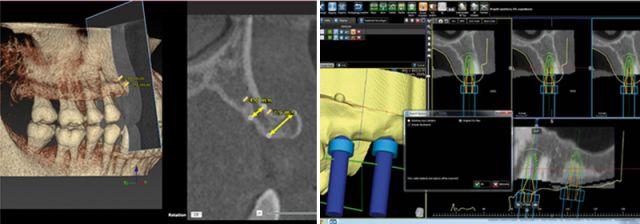

種植牙目前好選擇先進(jìn)的3D數(shù)字化全程導(dǎo)板種植牙技術(shù),根據(jù)數(shù)碼掃描,骨骼、神經(jīng)、血管等組織的三維模型重建,設(shè)計(jì)種植位置,選定合適的種植體,完全模擬顯示種植體在牙槽骨的位置,打印出導(dǎo)板模型,利用導(dǎo)板,確立種植體與牙頜竇底的距離、深度、種植體半徑、傾斜度等,按照種植導(dǎo)板導(dǎo)航種植,減少種植手術(shù)的時(shí)間,手術(shù)過程全程!華南目前在能開展這項(xiàng)技術(shù)的醫(yī)院中德倫口腔首屈一指。